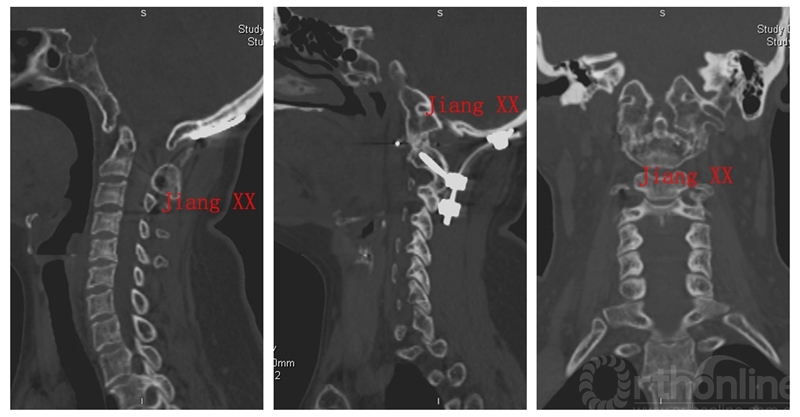

病例一:患者女性,49岁,因颈部活动受限4月入院,诊断为寰枢椎脱位,颅底凹陷。

术前CT

术后CT

术后一年CT